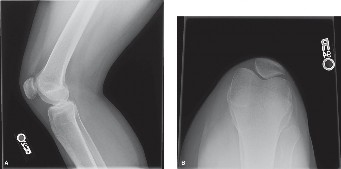

Standard radiographic evaluation of the knee is the first-line imaging modality for anterior knee pain. The patient's initial X-rays (Figures 9-1 A-C) include a weight-bearing anteroposterior (AP), a true lateral at 30 degrees of flexion, and an axial (Merchant or Sunrise) view.

The AP view demonstrates normal tibiofemoral joint spaces with no evidence of osteochondral lesions, loose bodies, or degenerative changes. The lateral view is scrutinized for patellar height. The Insall-Salvati ratio (the ratio of the patellar tendon length to the greatest diagonal length of the patella) is calculated at 1.05, which falls within the normal range (0.8 to 1.2), ruling out patella alta or baja. The lateral view also shows no evidence of trochlear dysplasia; the crossing sign is absent, and the trochlear bump is not prominent.

The Merchant view is arguably the most critical radiograph for this patient. It reveals a subtle lateral tilt of the patella and mild lateral subluxation. The sulcus angle measures 138 degrees (normal is typically <145 degrees), indicating adequate trochlear depth. However, the congruence angle is slightly lateralized, confirming the clinical suspicion of lateral patellar maltracking. There is no evidence of advanced patellofemoral osteoarthritis, osteophyte formation, or subchondral sclerosis.